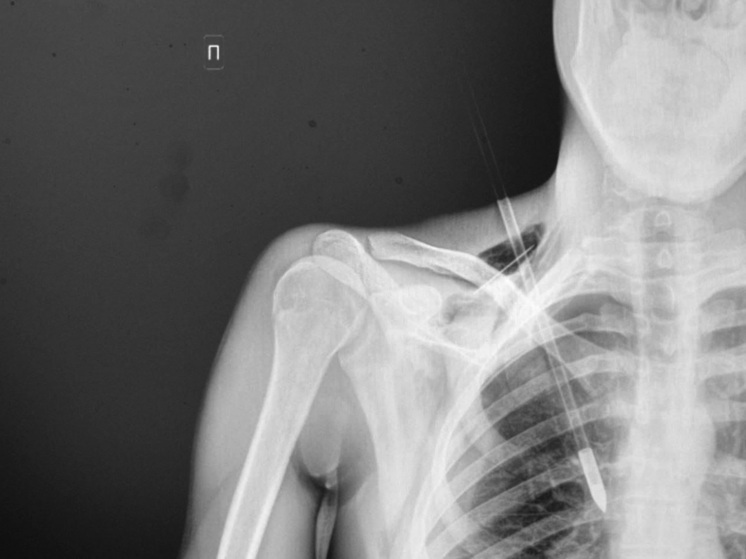

В миллиметрах от подключичной артерии прошла стрела, пронзившая грудь начинающего лучника в подмосковном Ступине. Она отрикошетила от дерева и воткнулась в плоть так глубоко, что доставать инородный предмет пришлось хирургам.

Фото: Минздрав МО

«Стрела прошла между ключицей и первым ребром, пробив верхушку легкого на глубину около 6 см, — рассказал врач-хирург Ступинской больницы Тимур Колесников. — К счастью, крупные кровеносные сосуды не пострадали, пациенту невероятно повезло. Мы успешно удалили инородное тело, а потом ушили поврежденное легкое и дренировали плевральную полость».